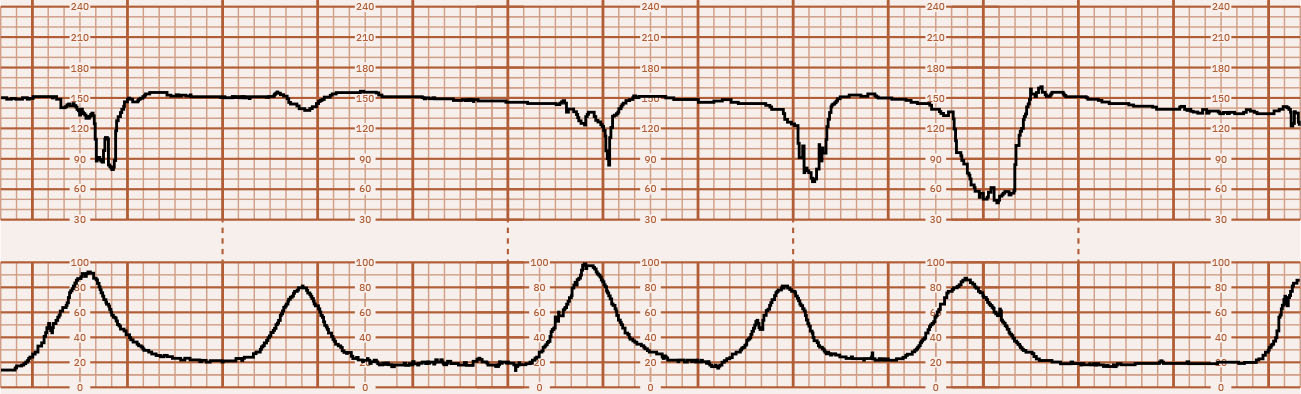

비정상 태아심박수(FHR) 및 자궁수축(UC) 양상은 흔히 산소 전달 중단, 과도한 자궁 작업부하, 일시적 약물 효과를 반영합니다. 가역적 생리 유발 요인과 진행성 병적 손상을 신속히 구분하는 것이 결과를 좌우합니다.

기저선 이상(빈맥, 서맥), 변이도 변화, 감퇴는 수축 맥락 및 모체 상태와 함께 해석합니다. 효과적인 간호는 표준화된 상급 대응 순서를 사용하면서 각 중재 후 반응을 반복 재사정합니다.

- 계층화 해석: Category I(안심), Category II(불확정), Category III(비정상/고위험).

- 범주 전환 단서: Category II는 혼합 중간 소견을 포함하며, Category III은 반복 지연 또는 가변 감퇴/서맥/동성파형과 함께 소실 변이도가 있을 때를 의미합니다.

- 동성파형 우려 단서: 실제 변이도 없이 매끄럽고 규칙적인 파형(about 3 to 5 cycles per minute)은 빈혈/출혈 맥락 같은 중증 태아 손상에 대한 긴급 평가가 필요합니다.